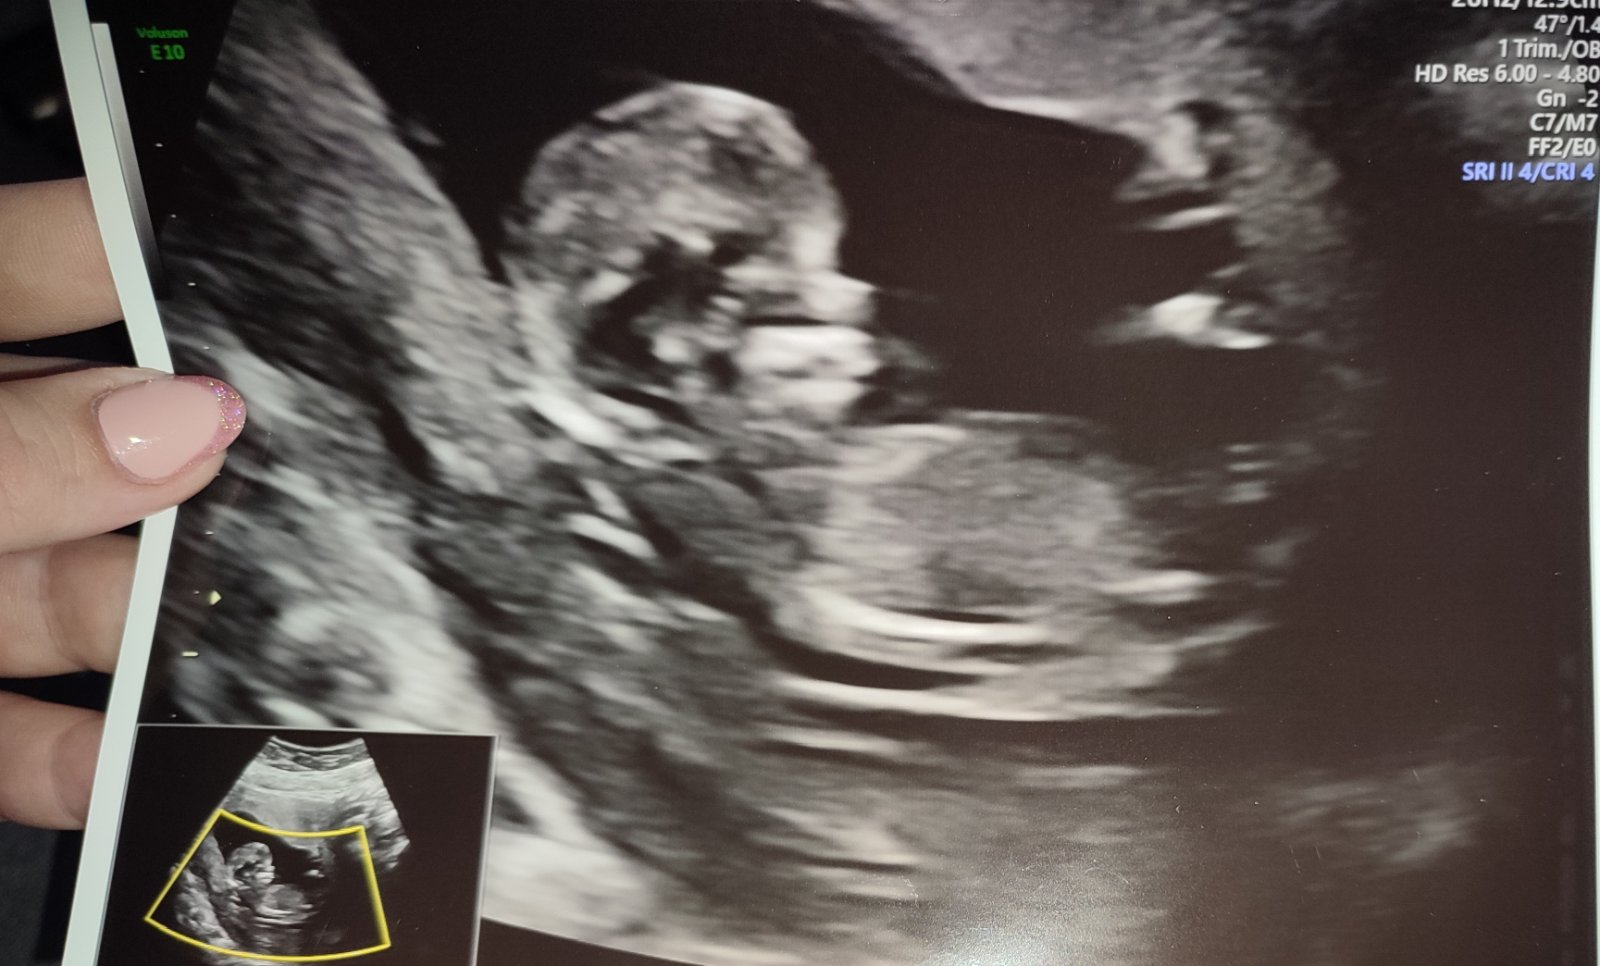

@lenulinka10 Miminko bylo mladší o 12 dní tak to dohání. Podle ultrazvuku co jsem byla dnes tak 10+5tt 😊

@kristynaprandl no to já jsem také zvědavá 🥰 tak na kontrole vse v poradku. Miminko je sice o 5 dní mladší,ale to vůbec nevadí. Krasne si tam kopalo a mavalo ručičkama🥰❤ ultrazvuk ma teda hroznou kvalitu,ale nevadí taky fotečka 🥰